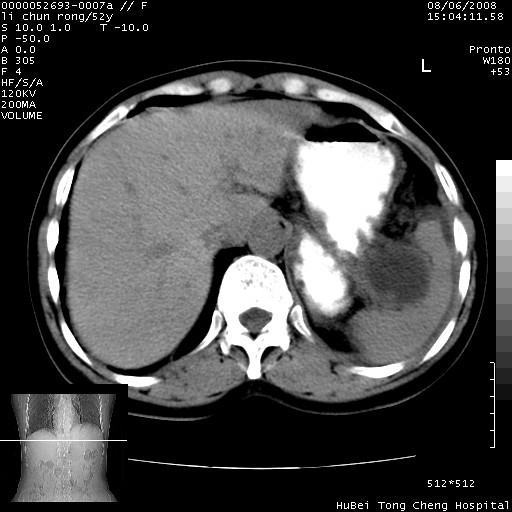

以下是引用云翔在2008-8-7 6:20:00的发言:[br]胰尾部囊性病变,考虑假囊肿,结合实验室检查疾病史

以下是引用zjzjr在2008-8-7 8:38:00的发言:[br]支持胰腺炎伴假囊肿形成,左肾小囊肿.少量腹水.

以下是引用随光逐影在2008-8-7 9:12:00的发言:[br]1)考虑胰腺炎伴假性囊肿形成可能性大;胰腺囊腺瘤待排。2)左肾小囊肿。3)少量腹水。